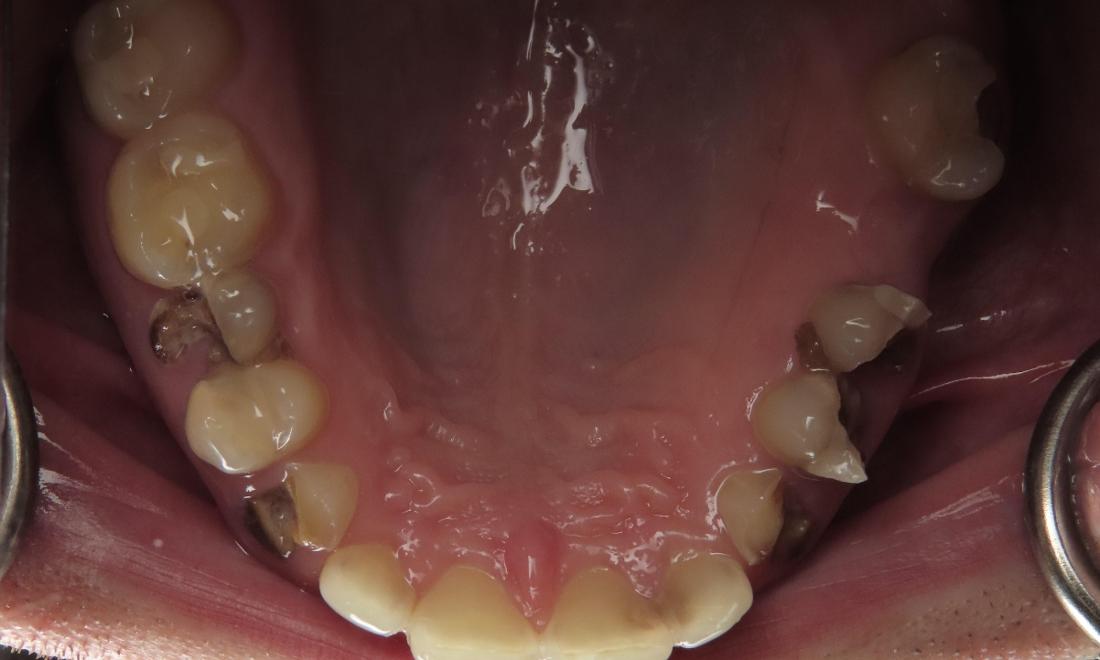

After a long journey to sobriety, this patient was ready to get his mouth healthy along with the rest of his body.  He was ready to smile with his kids again and jumpstart his new career.

Overhead view of mouth before complete smile makeover, nashville tn Overhead view of mouth after complete smile makeover, nashville tn